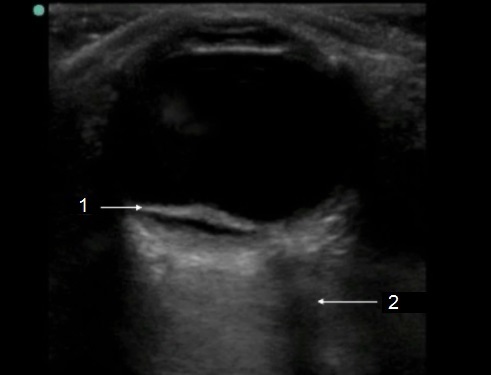

Ocular Retinal Detachment 2 Image

Retinal Detachment (RD)

Optic Nerve